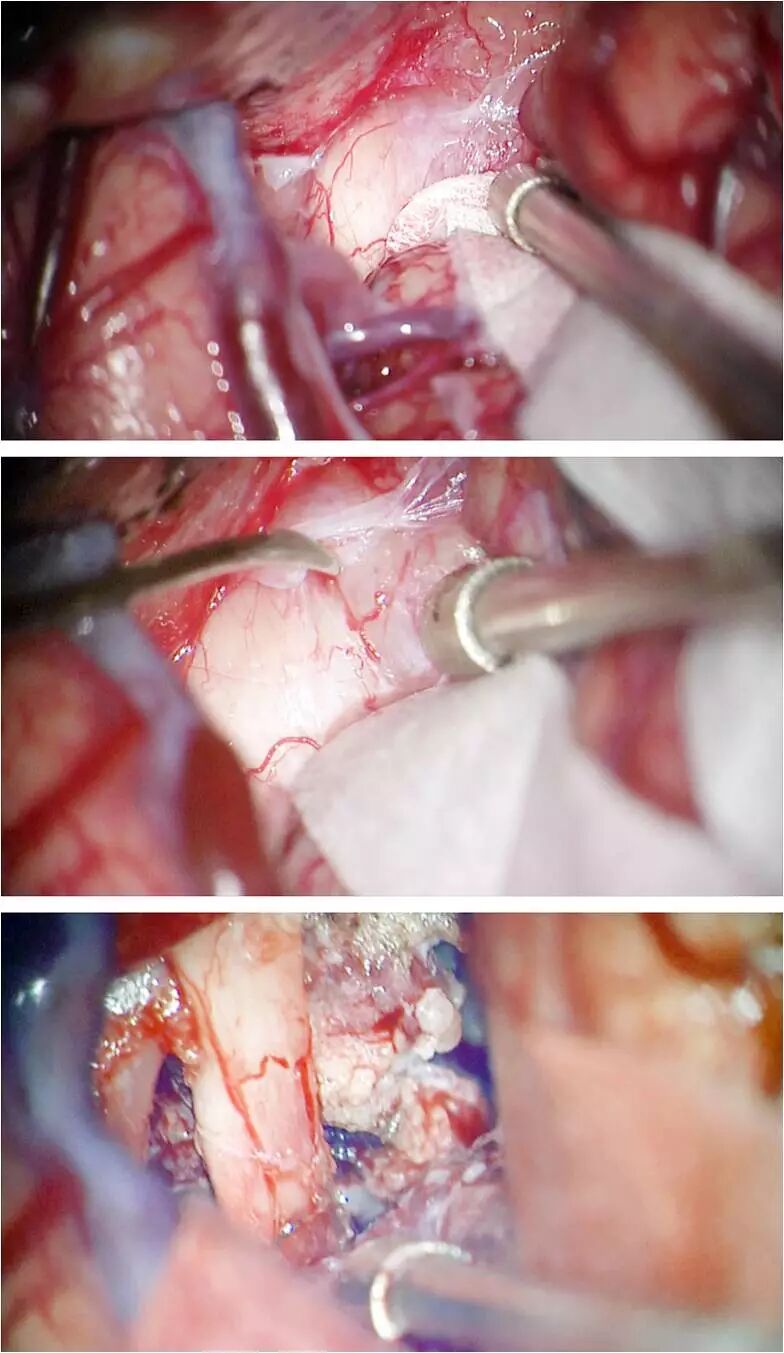

图14. 通过左侧翼点入路切除一例大型TSM。最初的探查发现视神经和肿瘤粘连很紧密(上图)。解剖蛛网膜后可逐步建立一个安全的分离界面(中图)。随后减压肿瘤并锐性分离使肿瘤能够被牵离视神经(下图)。